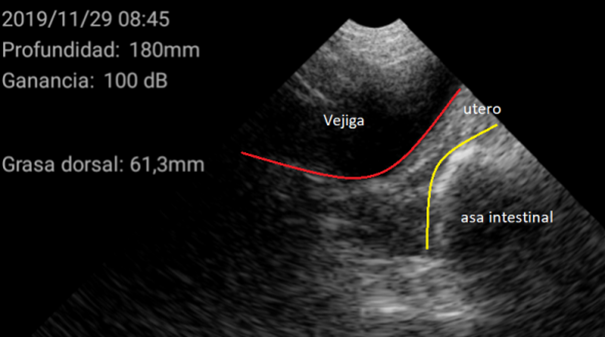

El diagnóstico se basó en la determinación del tamaño del útero y su posición en relación con otras estructuras como la vejiga urinaria o las asas intestinales. En general, se encuentra en posición ventral a la vejiga. Cuando el tamaño del útero es pequeño, ocupa muy poco espacio en la pantalla, de esta manera se considera una hembra impúber.

Por el contrario, úteros grandes, con cuernos uterinos identificables y que ocupan gran superficie de la pantalla se consideran como hembra púber.

Imágenes de cerdas Púberes con el ecógrafo W3 de Kubus